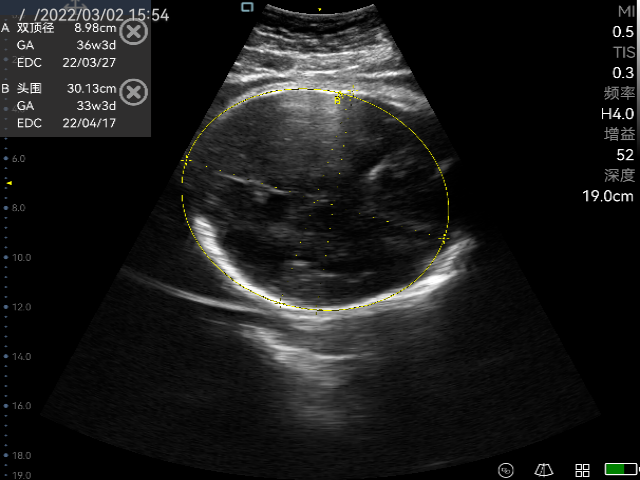

Obstetric ultrasonography is one of the routine prenatal examination items. The ultrasonic diagnostic instrument is used to scan various sections of the human body. According to the amplitude of the echo signal, real-time imaging is performed on the monitor, so it can detect the uterine appendages and the fetus. Through the biological measurement of the fetal head, abdomen, long bones, etc., the gestational age and the size of the fetus can be estimated. Through the observation of real-time dynamic ultrasound images, it is possible to detect whether the fetus has structural abnormalities, determine the degree of fetal malformation, evaluate the prognosis, whether clinical treatment is required to preserve fetal survival. For pregnant women with no abnormal performance within ten weeks, no ultrasound examination is required. For older and high-risk pregnancy, obstetric ultrasound examination must be performed regardless of the gestational age, which not only ensures the safety of the fetus, but also prepares for delivery. Ultrasound is widely used in obstetrics because of its non-radiation, simple operation, flexibility and convenience, high resolution, and moderate examination price.

The practical application of P50 in obstetrics

Perioperative period is helpful for doctors to assess the real-time labor processes of the placenta, amniotic fluid etc.

Ultrasonography in early, middle and third trimester, obstetric Doppler ultrasound, normal twin pregnancy, ultrasound diagnosis of common fetal structural malformations, twin pregnancy complications, abnormal pregnancy, abnormal pregnancy appendages, real-time monitoring of midwifery, etc.